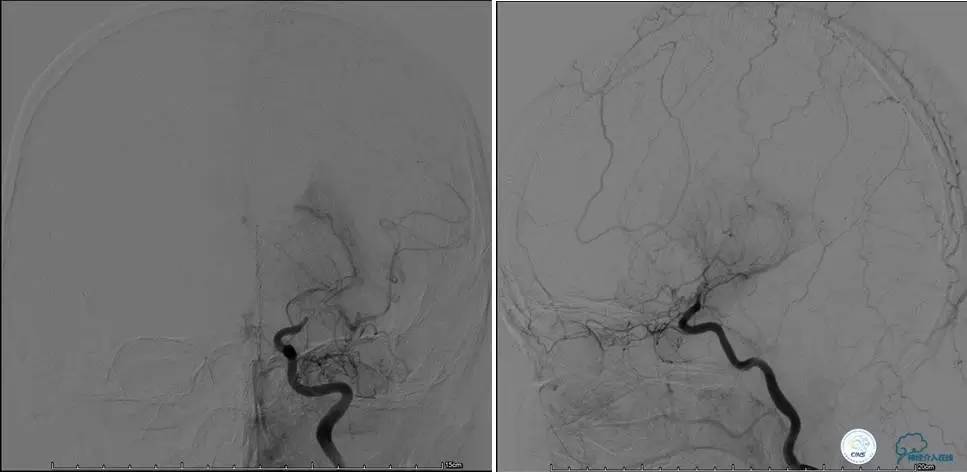

▼DSA示右侧椎动脉发育低下,弥漫性狭窄,可以看到左侧椎动脉反流,因此判断左侧椎动脉V4段CTO。

治疗:

微导丝穿过闭塞段,微导管造影,球扩闭塞段,置入Wingspan支架,血流完全恢复正常。

患者术后2天再次出现卒中发作,药物治疗好转,此后病情稳定。半年后复查DSA,见支架闭塞,侧支循环开放。患者一般情况好,mRS:1分。